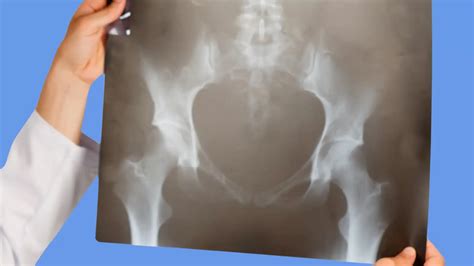

Diagnosing hip joint effusion typically involves a combination of physical examination, medical history, and diagnostic tests. The diagnostic process may include:

• Imaging Tests: X-rays, MRI, or ultrasound to visualize the hip joint and detect fluid accumulation.